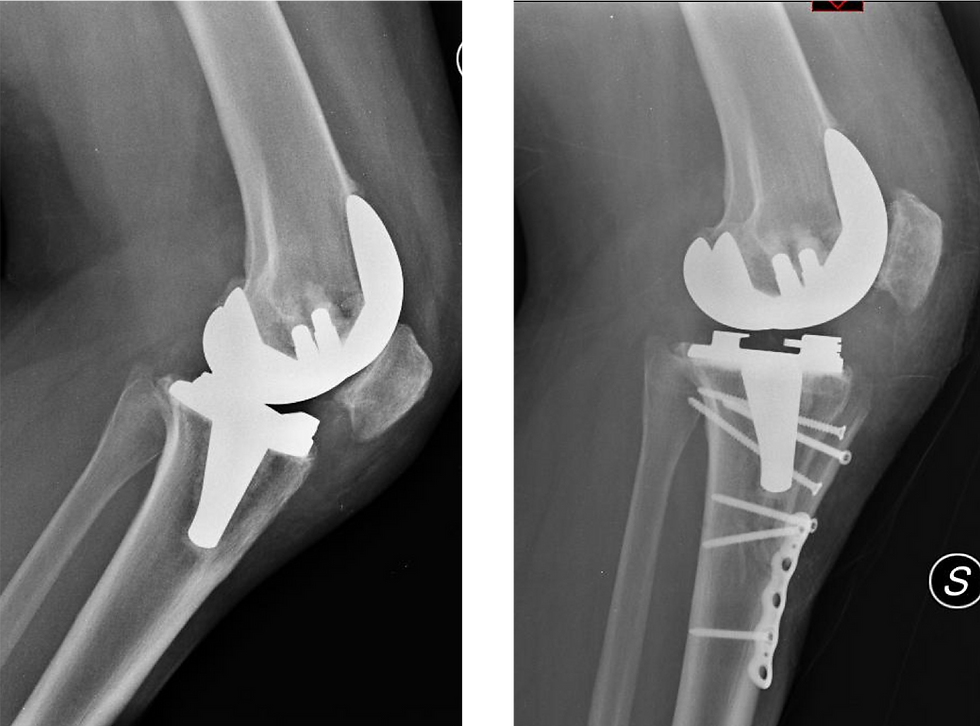

Paziente di 41 anni operata altrove di artroprotesi del ginocchio.

Alla radiografia in laterale si nota che la rotula è molto bassa, “incastrata” fra i condili e impedisce la flessione.

La paziente lamenta dolore, ed una escursione articolare molto limitata.

Nel tentativo di risolvere ha già eseguito 2 artroscopie senza successo.

Eseguite la radiografia assiale del ginocchio si rende evidente che la rotula è fuori sede, lussata lateralmente.

Il mancato allineamento della rotula è la fonte dei disturbi accusarti dal paziente.

Radiografie prima e dopo l’intervento correttivo

A dx si noti come la rotula sia ora in una posizione fisiologica.